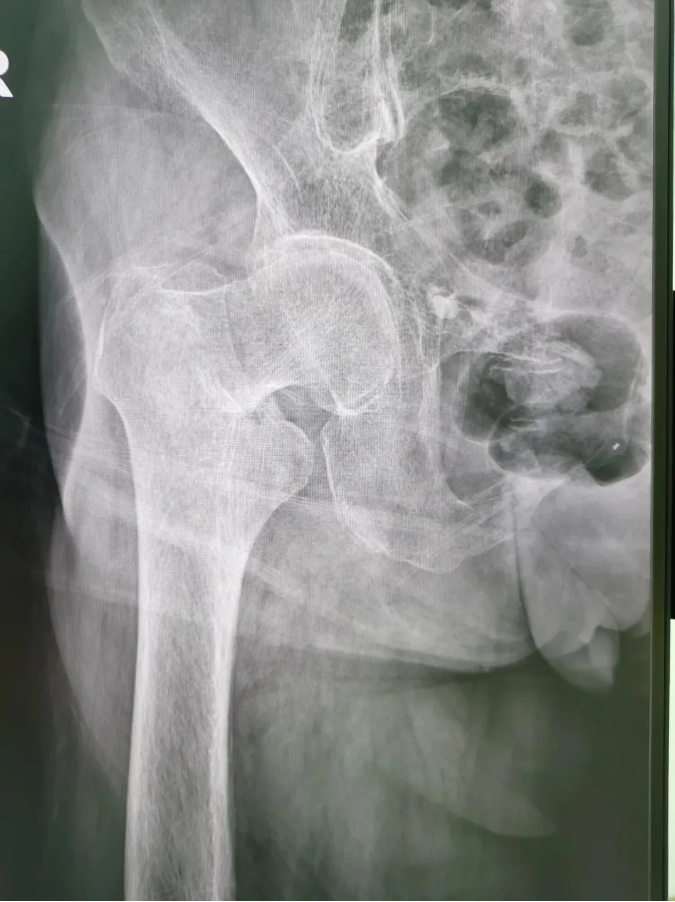

今年91歲的陳婆婆,9月份時在家不慎摔倒,右臀部著地,當(dāng)下感到髖部劇烈疼痛并活動受限。為求進(jìn)一步治療,到順德和平外科醫(yī)院骨三區(qū)就診,該區(qū)主任楊升平主任為其診療,被診斷為“右股骨頸骨折”,需進(jìn)行右股骨頸骨折經(jīng)皮閉合復(fù)位空心螺釘內(nèi)固定手術(shù)。

術(shù)前X光

陳婆婆91歲的高齡,有高血壓和冠心病病史,通過傳統(tǒng)開刀手術(shù)治療風(fēng)險較大。經(jīng)骨三區(qū)專業(yè)醫(yī)療團(tuán)隊(duì)討論,決定讓天璣?骨科機(jī)器人上場,輔助完成微創(chuàng)手術(shù)。